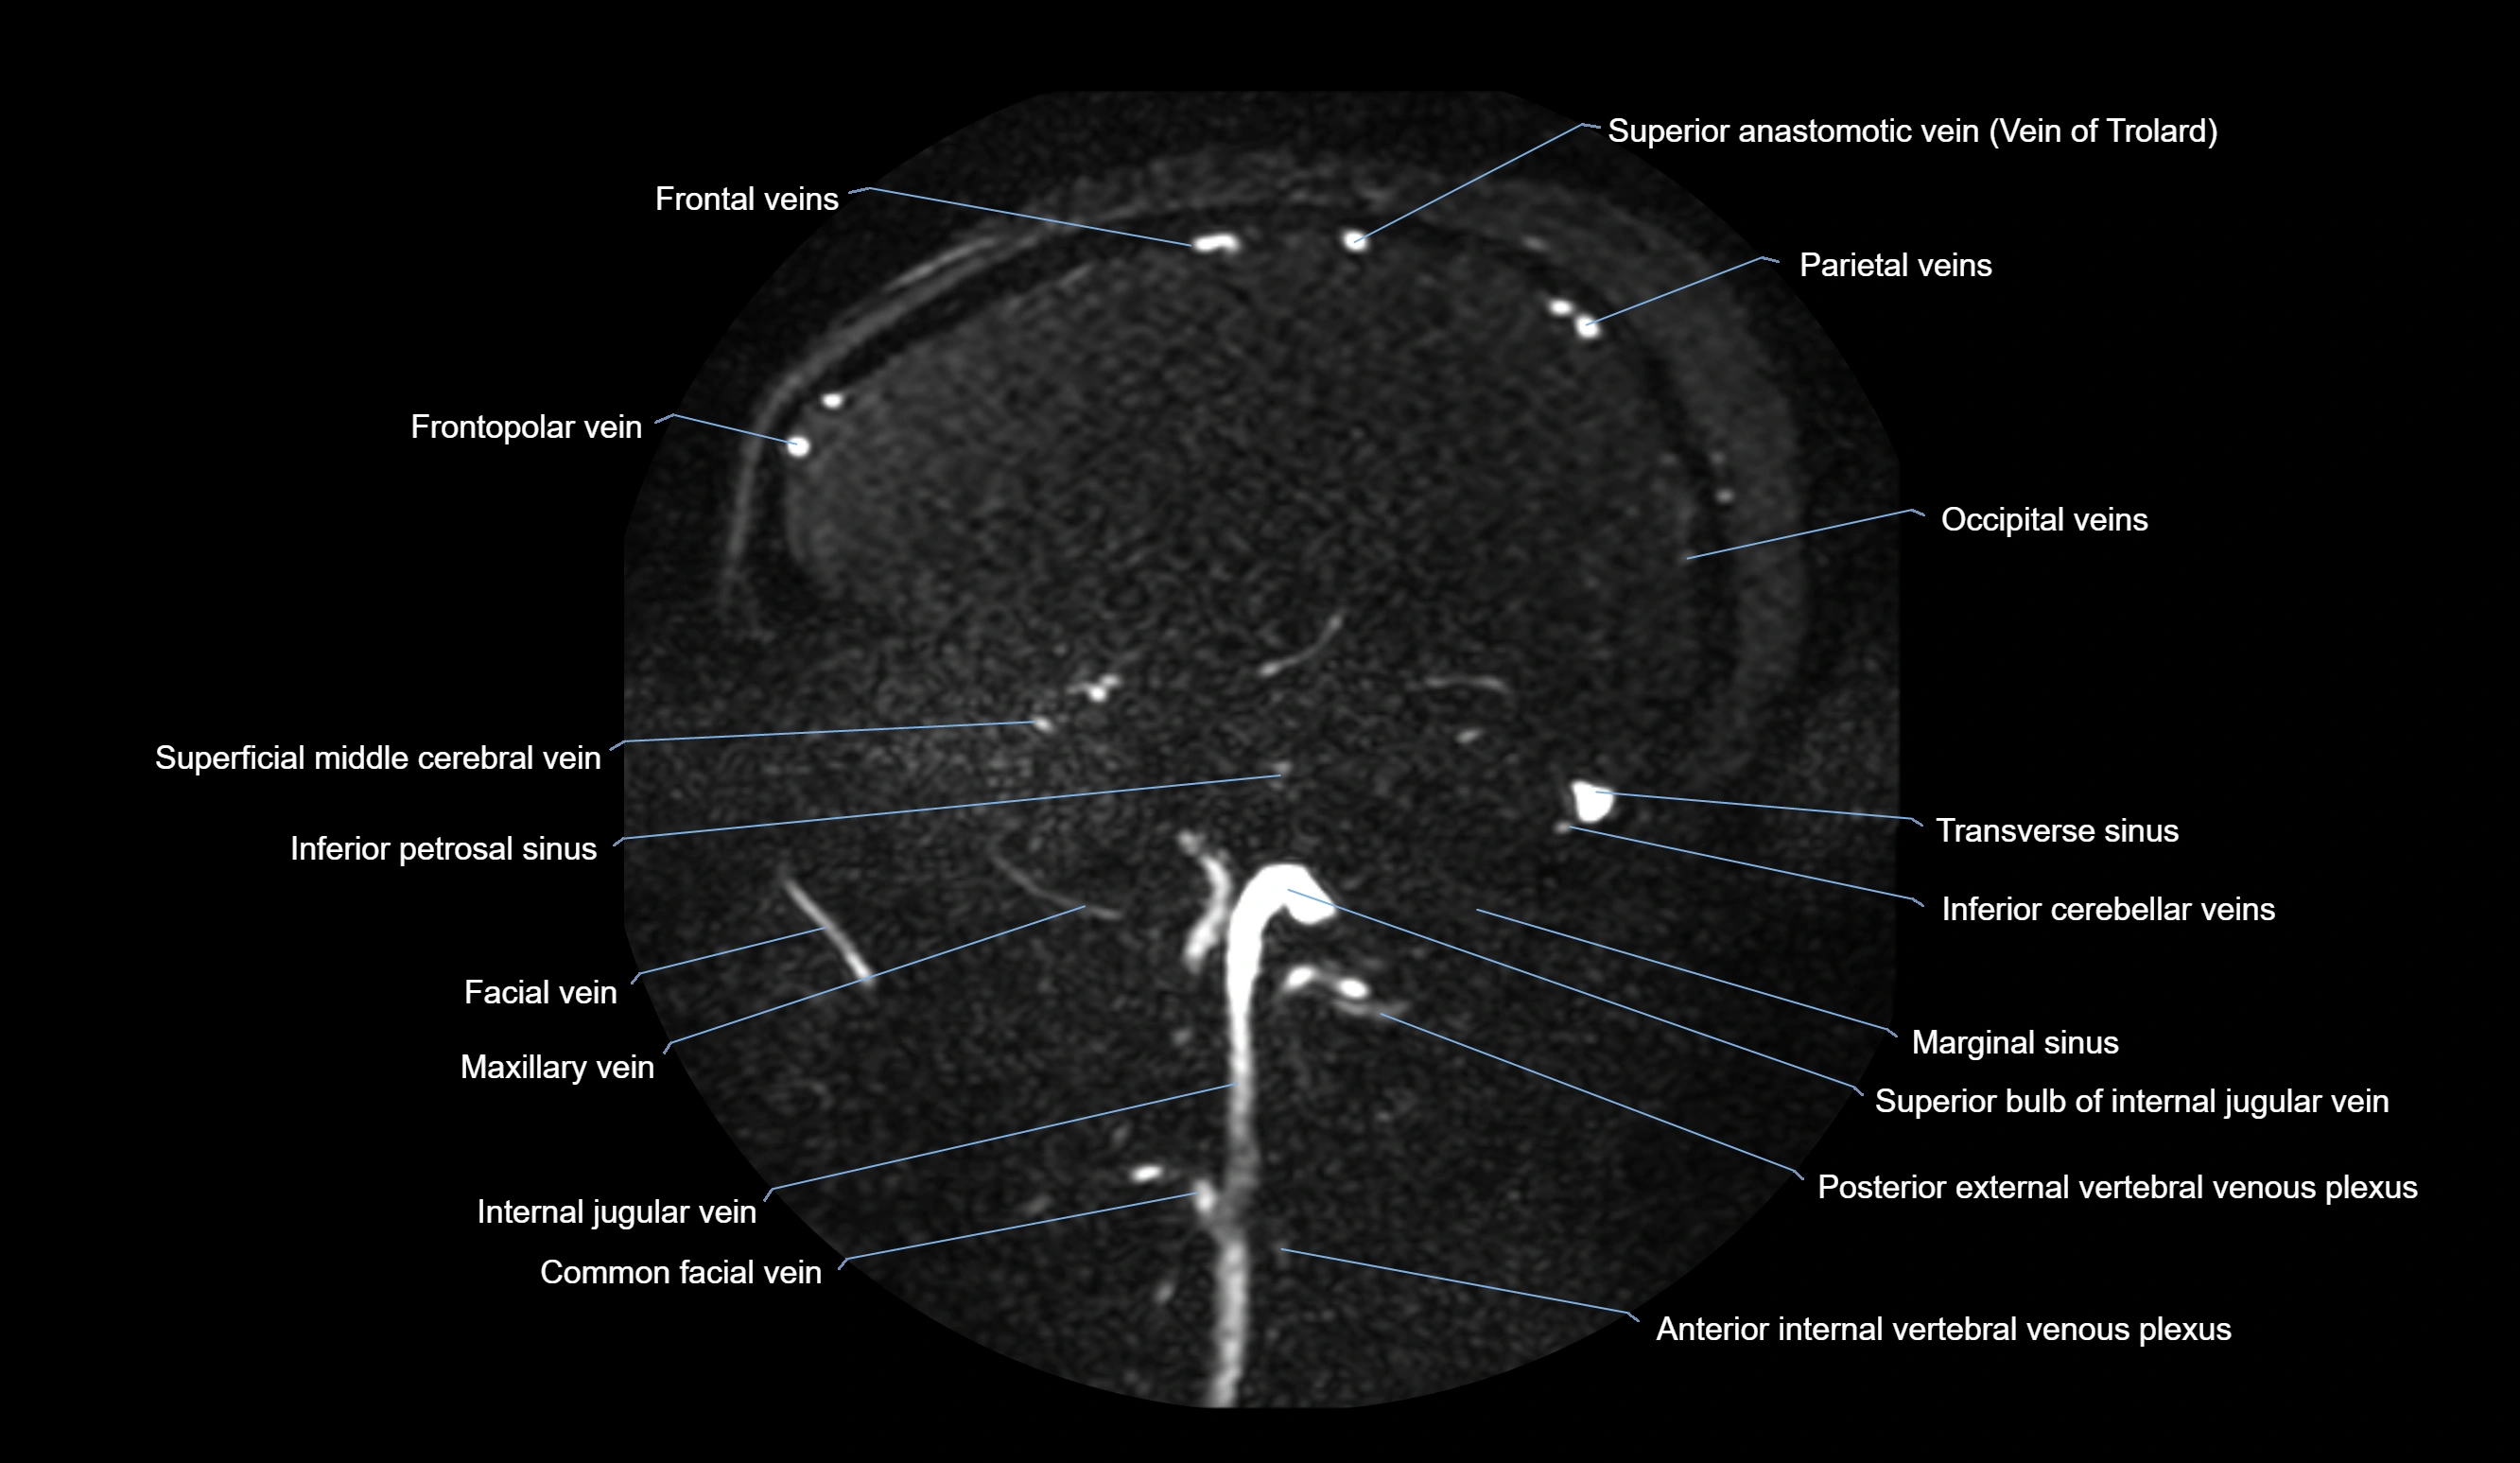

MR Venography (MRV):

• Time-of-flight (TOF) or contrast-enhanced MRV shows the angular vein as a bright enhancing venous channel

• Clearly demonstrates its continuity with the facial vein and superior ophthalmic vein

• MRV is highly useful in evaluating thrombosis, venous obstruction, or collateral venous drainage

CT Venography (CTV):

• Clearly visualizes the angular vein as a contrast-filled venous channel

• Demonstrates its communication with the facial vein, superior ophthalmic vein, and cavernous sinus

• Essential for detecting facial vein thrombosis, orbital venous involvement, and cavernous sinus pathology

MRI images